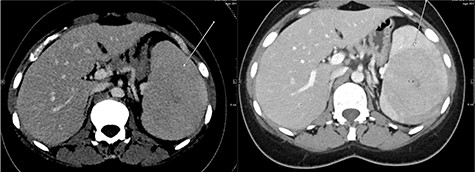

A multi-planar, multi-sequential abdominal magnetic resonance imaging (MRI) without contrast showed a well-circumscribed splenic mass with patchy nodular enhancement, which became more diffuse on delayed images and had low T2 signal and isointense T1 signal with no diffusion restriction (Fig. 3). There was no evidence of lymphadenopathy and no features favoring a lymphoma. The splenic mass was diagnosed as SANT, with plans to follow it with serial imaging.

(Top) coronal T2 WI MR Image showing a hypointense lesion in the spleen, which is not showing any diffusion restriction (right image); (middle images) post-contrast axial T1 WI MR image showing hypointense lesion with patchy contrast enhancement in the center (middle right image); the lesion becomes further isointense on delayed image (middle left image); (bottom) MRI of abdomen T1 weighted axial (bottom left) and coronal (bottom right) post-contrast images showing a lesion in the spleen (arrow) with peripheral and septal enhancement with a hypoenhancing center.